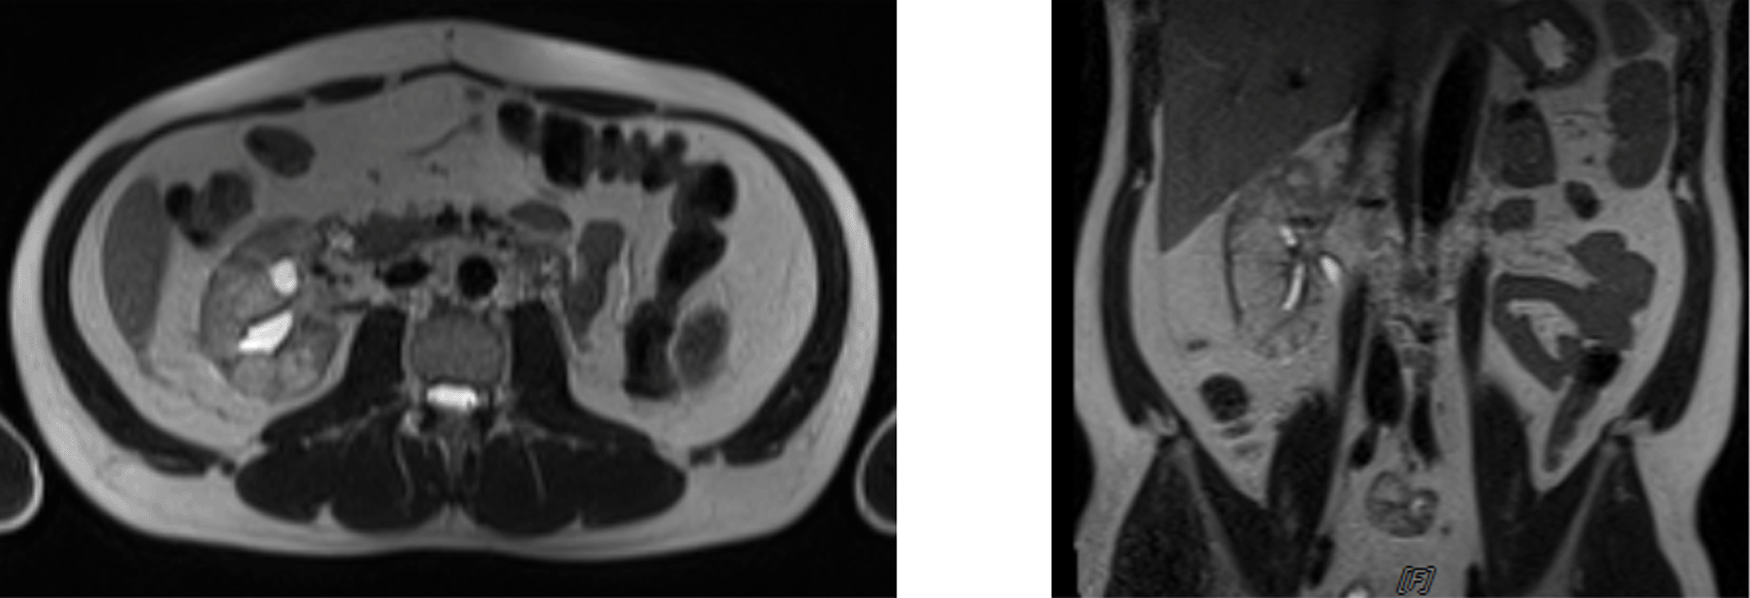

The patient was given intracavitary chemotherapy using gemcitabine through nephrostomy. Furthermore, cystoscopy intracavitary instillation of chemotherapy agent using gemcitabine was administered through nephrostomy. The examination conducted in September 2020 showed a normal right kidney with no hydronephrosis, but there was a sign of intraluminal neobladder clotting. The patient then went to a clot evacuation cystoscope, and the last cycle of intracavitary gemcitabine was given in November 2020. Furthermore, an MRI and ureterorenoscopy were conducted and the mass was shown to be decreased. Abdominal MRI in May 2021 showed benign calyx dilatation suspicious due to stricture and heterogeneous renal parenchyma (Figure 5).